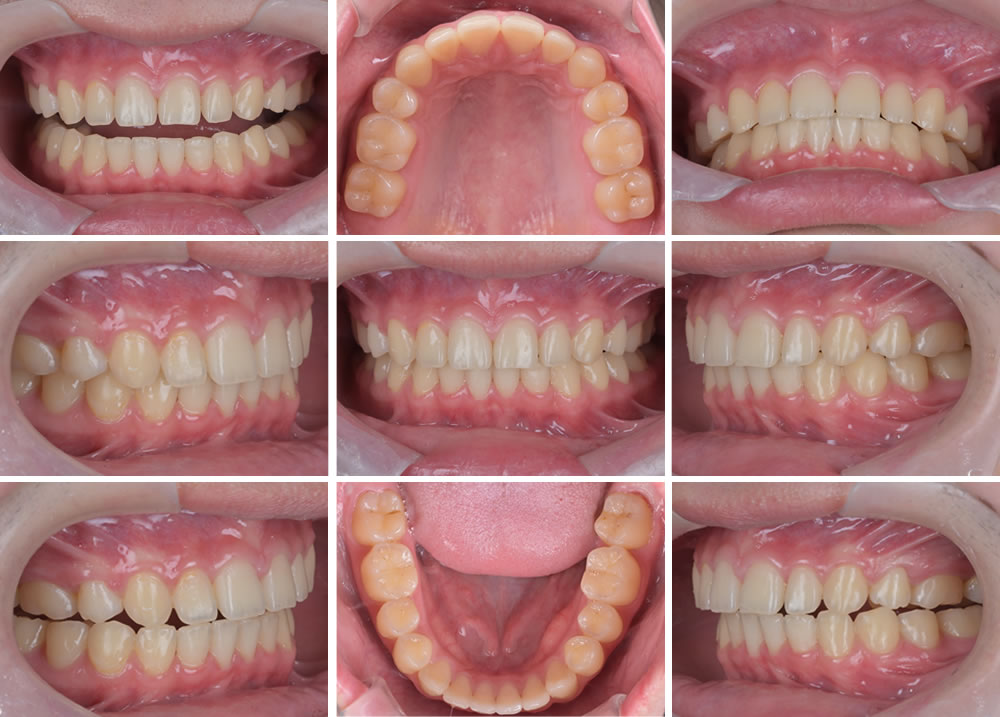

矯正治療終了

こちらが矯正終了時の写真です。上顎前歯の突出感もなくなり全体的に綺麗になりました。

保定処置

最後はリテーナー(保定装置)を装着してもらい終了です。